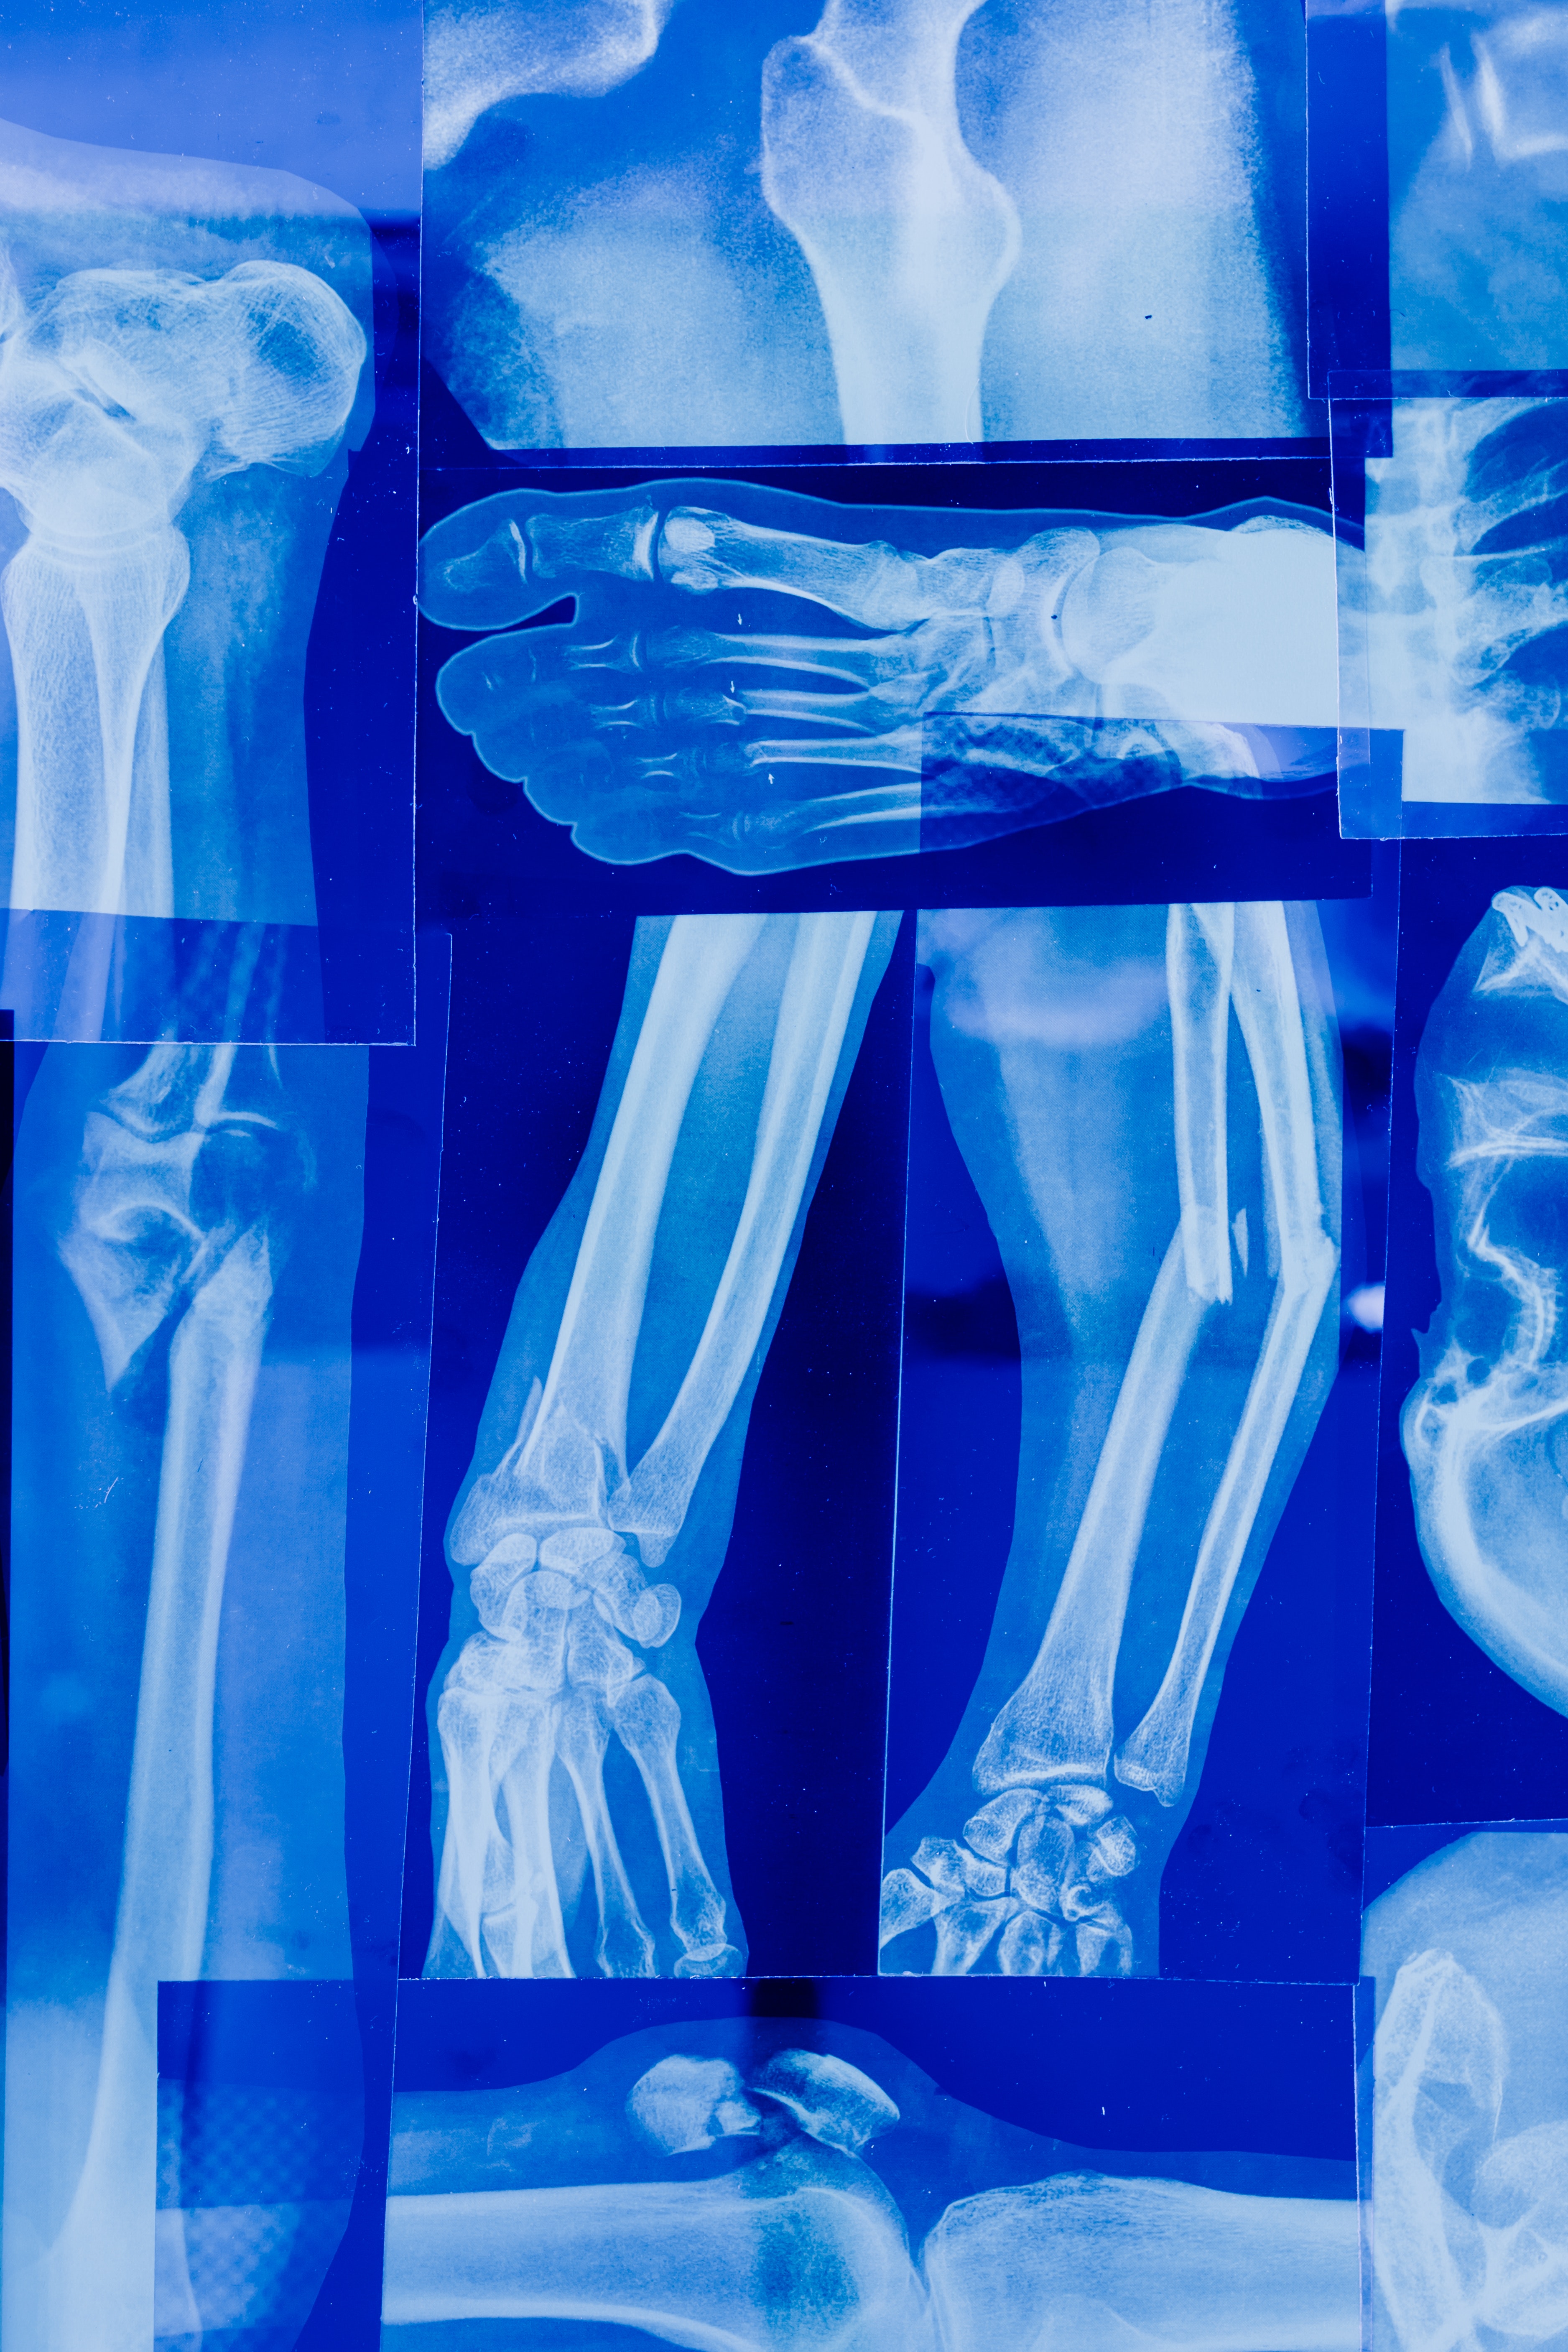

MSM은 관절 건강에 유익한 영향을 미치는 것으로 알려져 있습니다.

MSM은 염증을 줄이고 관절의 운동성을 향상시켜 운동 선수들과 관절염이 있는 사람들에게 도움이 될 수 있습니다.